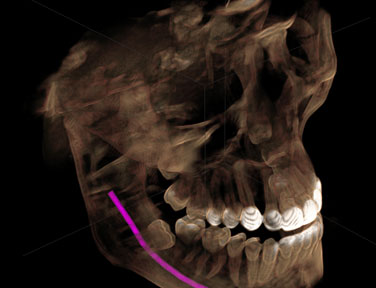

For the first time in the 100-year history of dental X-rays (radiography), an extraordinary new technology surpasses the diagnostic abilities of traditional film. It does so with substantially less radiation exposure to you.. and us. This system has truly amazing diagnostic tools, making the image quality simply unmatched.

Lockheed Martin, the aerospace manufacturer of the Magellan Venus Spacecraft and the Hubble Telescope designed the digital X-ray sensor that is the heart of this technology. The sensor is very special as it has a uniquely shaped design for your optimum comfort. No more sharp edges like the old film had. This allows for increased positioning accuracy.

This system allows for the ability to instantly produce the very best possible diagnosis and produces up to 90% less radiation.